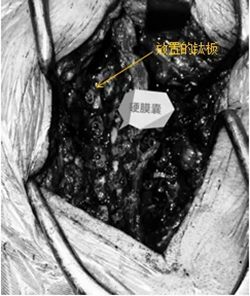

3. 重建稳定:

采用微型钛板+螺钉固定,术中透视确认位置;

喷洒生物材料+覆盖可吸收防粘连膜;

放置引流管,逐层缝合。

▲ 手术示图